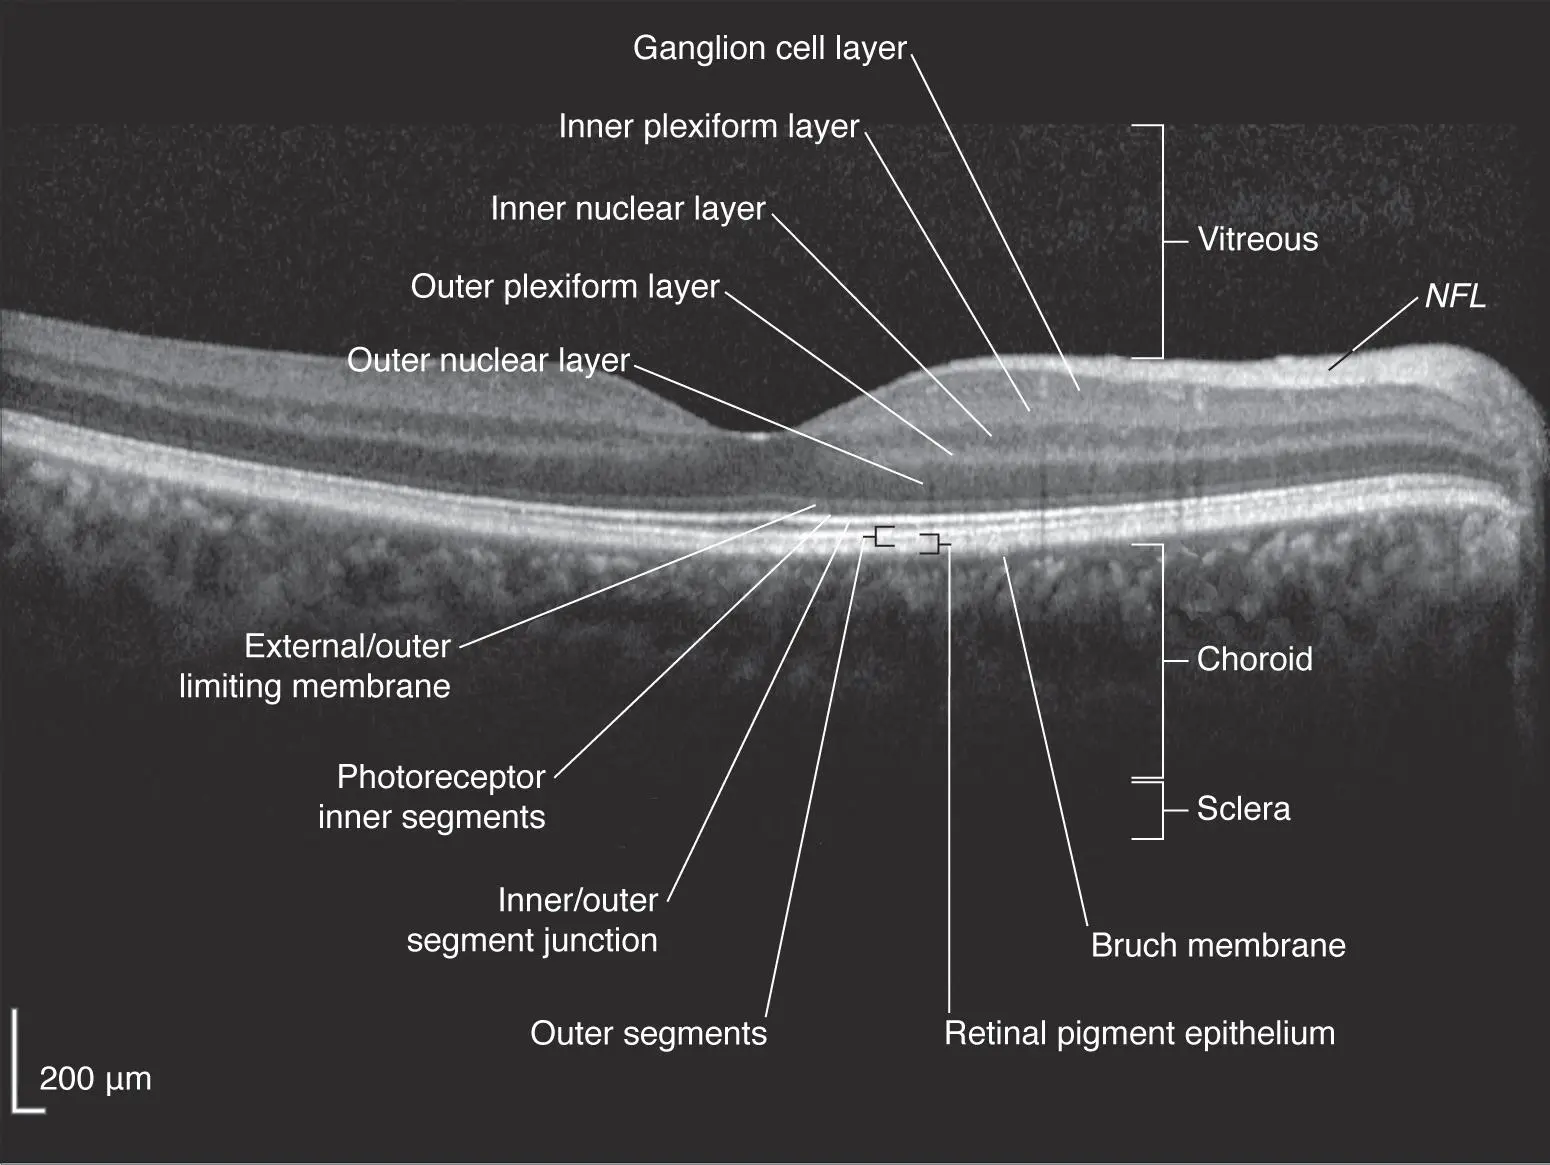

The OCT is one of the most important tests that a retinal ophthalmologist performs in order to diagnose and treat macular degeneration. It is a non-invasive technique that shows a cross-sectional view of the retina. It uses light - it is not an xray. As you can see in this normal OCT, the retina is composed of many layers. In addition to the retina, we also look at the area in front of the retina (vitreous) and behind the retina (choroid).